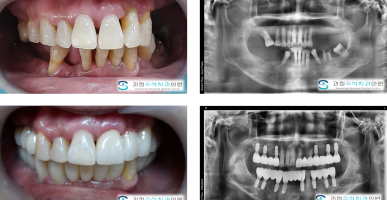

골융기제거술

혀아래쪽으로 울퉁불퉁한 잇몸뼈 골융기(토러스)를 제거한 사례입니다.